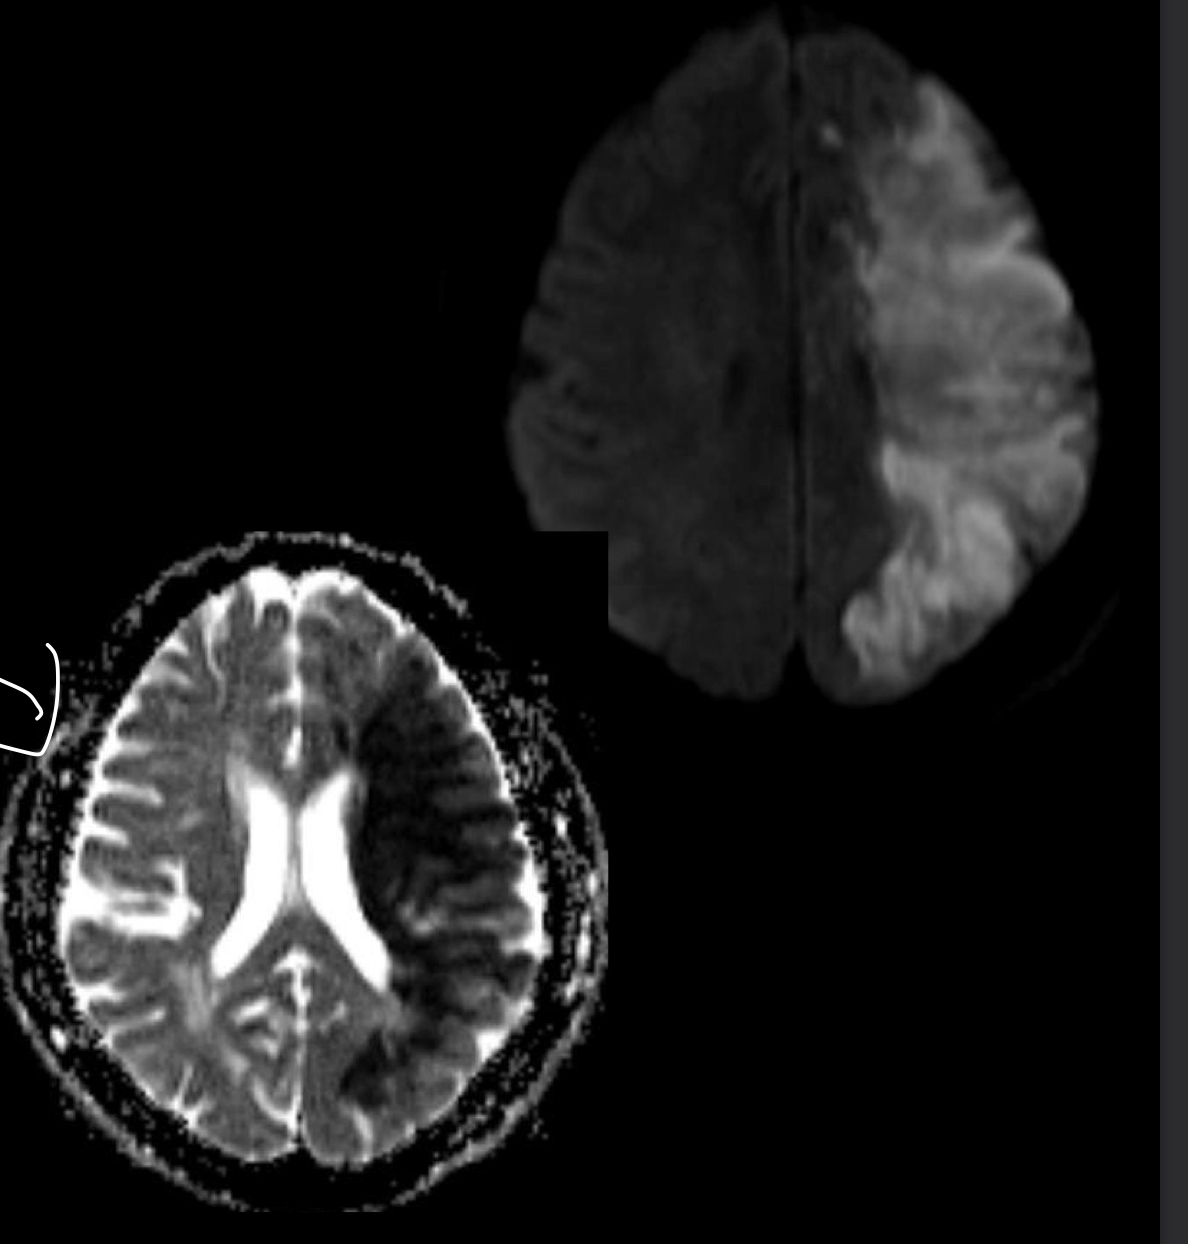

Q

Qué es?

A

RM de EVC isquemico

Que secuencia se usa en RM para ver EVC agudo?

DIFUSION DWI /ADC